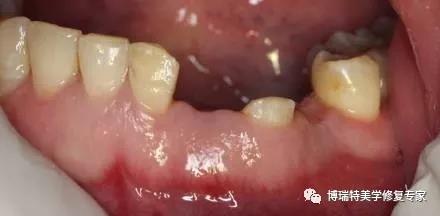

3.软组织瓣的早期裂开或穿孔

种植体上部过早暴露常发生于二段式植入种植一期手术后软组织瓣的早期裂开或穿孔,前磨牙区和磨牙区多发。目前认为,缝合过紧导致局部血供不足,覆盖种植义齿的软组织瓣血液循环障碍致组织坏死是导致软组织瓣裂开或穿孔的主要原因。邱立新等。认为下颌磨牙区牙槽嵴顶出黏骨膜较薄是该区域易发生软组织瓣裂开或穿孔的主要原因。另有研究表明,下颌磨牙区的切口设计对软组织裂开或穿孔有一定的影响,当该区域切口设计为偏舌侧切口时较易发生裂开或穿孔。软组织瓣裂开或穿孑L会影响伤口的愈合,引起种植体周围炎及种植体的早期暴露。有国外学者指出因软组织裂开或穿孔而导致的种植体早期暴露还可引起种植体颈缘处骨吸收,其机制并不清楚,可能与裂开的软组织瓣产生盲袋,引起厌氧菌的滋生有关。

如果出现软组织的裂开或穿孔,要应用过氧化氢溶液、生理盐水进行局部冲洗,之后进行复位缝合或软组织移植处理。为避免软组织瓣的裂开或穿孔手术时尽量避免在张力下缝合,术后应保持口腔卫生。